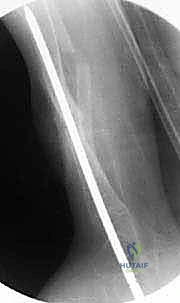

الخطوة الرابعة: تجهيز القناة النخاعية

باستخدام أدوات حفر دقيقة (Reamers)، يتم فتح وتوسيع القناة النخاعية المسدودة في كل من الجزء العلوي والسفلي لقصبة الساق. يجب أن يكون الحفر دقيقاً لإنشاء مسار مستقيم يسمح بمرور القضيب المعدني.

الخطوة الخامسة: إدخال قضيب ويليامز

يتم اختيار قضيب ويليامز بالطول والسمك المناسبين بناءً على قياسات دقيقة. يتم إدخال القضيب من أعلى قصبة الساق (قرب الركبة) أو من أسفلها، ليخترق القناة النخاعية، ويعبر منطقة الكسر، ليصل إلى الجزء الآخر من العظم، مما يضمن استقامة الساق وتثبيت الكسر بقوة.